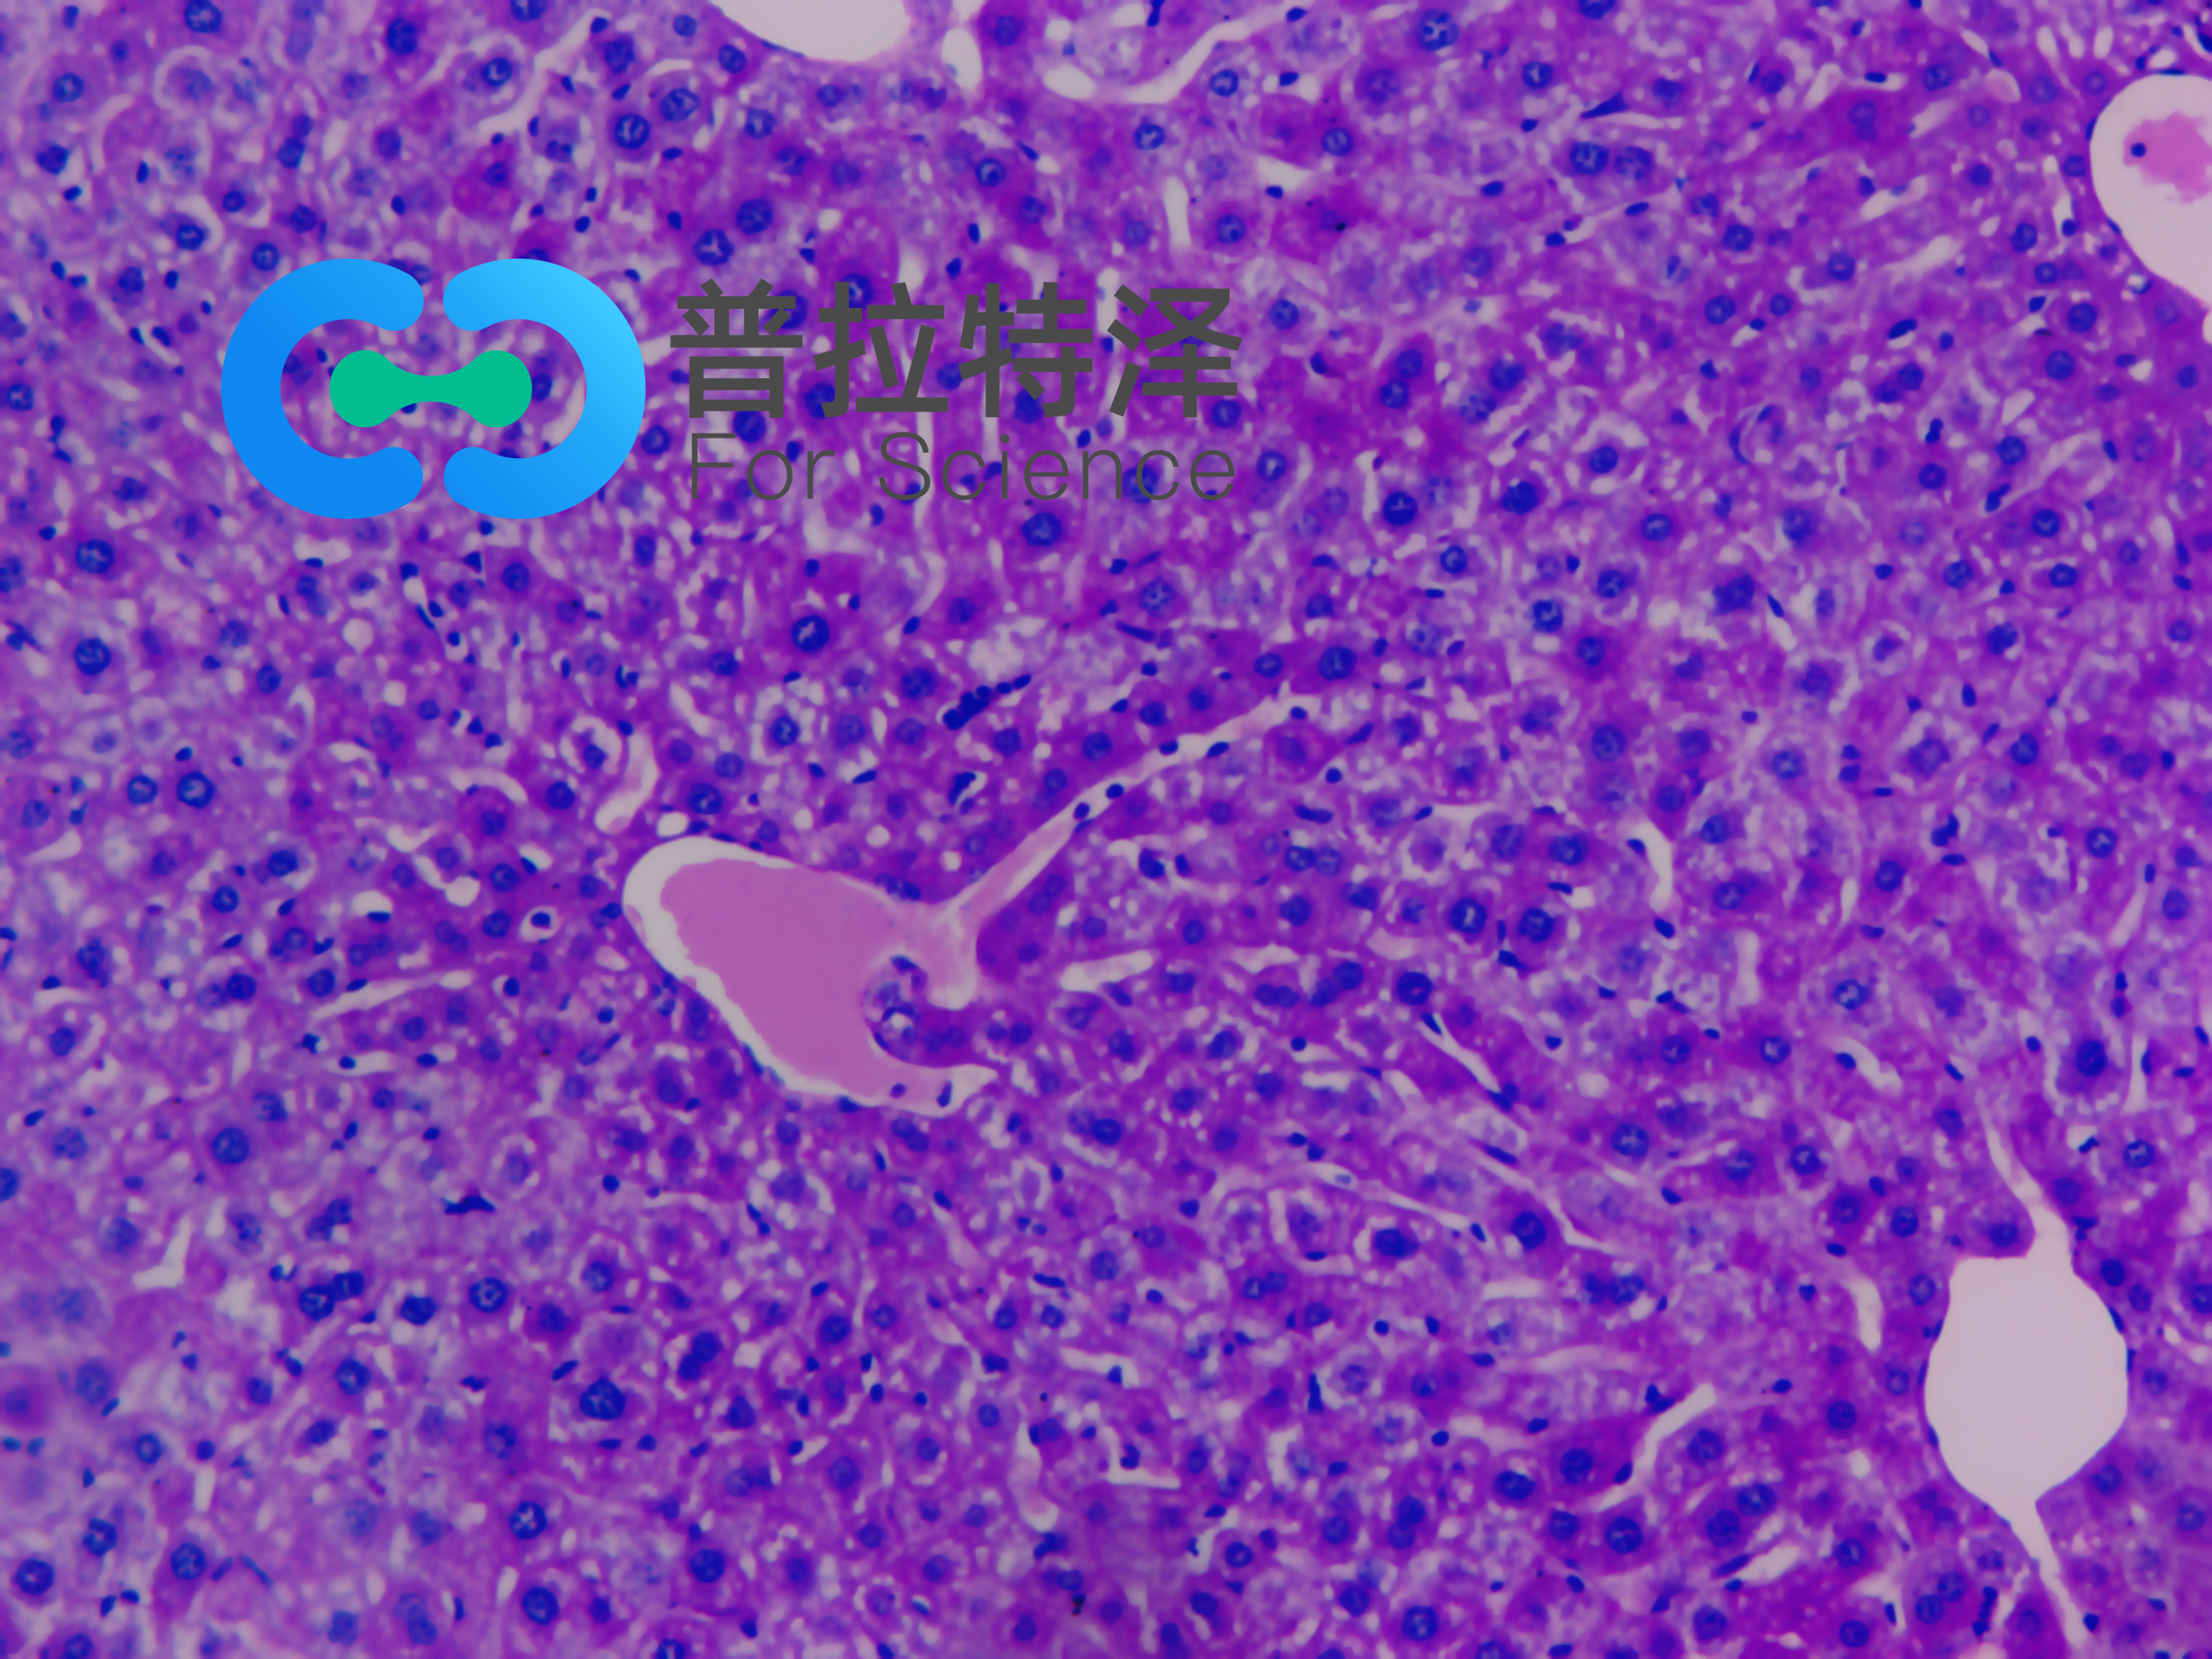

實(shí)驗(yàn)簡(jiǎn)介:PAS染色又稱過(guò)碘酸雪夫染色,糖原染色。一般用來(lái)顯示糖元和其它多糖物質(zhì)。

實(shí)驗(yàn)原理:糖原染色是病理學(xué)中常規(guī)的染色方法之一,氧化劑能氧化糖類及有關(guān)物質(zhì)中的1,2-乙二醇基,使之變?yōu)槎┡cSchiff試劑能結(jié)合成一種品紅化合物,產(chǎn)生紫紅色。PAS技術(shù)常用來(lái)顯示糖原和其他多糖,該染色液不僅能夠顯示糖原,還能顯示中性黏液性物質(zhì)和某些酸性物質(zhì),以及軟骨、垂體、霉菌、真菌、色素、淀粉樣物質(zhì)、基底膜等。

隨著醫(yī)學(xué)實(shí)驗(yàn)技術(shù)的發(fā)展,近年來(lái),糖原染色應(yīng)用的范圍更加廣泛,如用以證明與鑒別細(xì)胞內(nèi)空泡狀的性質(zhì),心肌病變及其他心血管疾病的診斷,糖原累積病診斷和研究,糖尿病的診斷和研究,用于某些腫瘤的診斷等。除用于糖原的鑒定和黏液的顯示外,還可以觀察腎小球基底膜、結(jié)腸杯狀細(xì)胞中性黏液物質(zhì)、阿米巴滋養(yǎng)體和霉菌的著色。為臨床診斷、分類和治療提供了重要的依據(jù)。